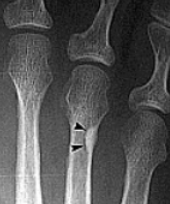

| Describe the alignment of metatarsal 2 | There is no angulation nor displacement of the distal segment relative to the proximal segment. |

| Describe the alignment of metatarsal 3 | The distal segment is displaced laterally (50% apposition) and angulated medially. |

| Describe the alignment of metatarsal 4 | The distal segment is displaced laterally (75% apposition) but there is no apparent angulation. |

| Describe the tubulation of the metatarsals | Metatarsals are overtubulated - decreased girth. |

| Describe the tubulation of the metatarsals | Metatarsals are undertubulated - increased girth. |